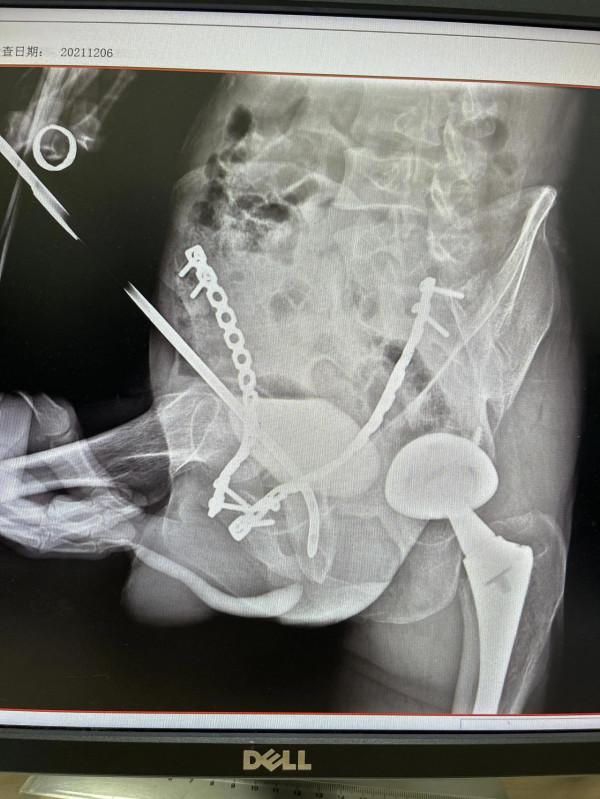

進而,患者慕名前來我的工作室求治。術前排洩性膀胱尿道造影,造影劑不能進入後尿道,後尿道不顯影。膀胱尿道會師造影示:膜部尿道閉鎖近2釐米(圖)。遂於今日在“硬膜外麻+腰麻”下行國內外領先的獨創性新手術“套筒穿刺導航+直徑匹配性遞增性尿道內切開術”。